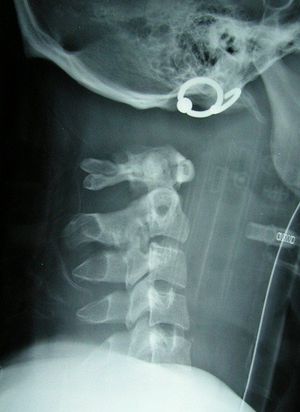

What is your diagnosis???

Cervical spine fracture .....and the patient has been intubated

Atlantoaxial subluxation

Can we say , total body dislocation , hanging

Jeepers oxipital atlanto dislocation

Internal decapitazation

Separated c-spine, usually fatal!

I wonder what are those rings doing on the throat.

They are ear rings. That isn't the throat; But the ears. Due to internal decapItation.